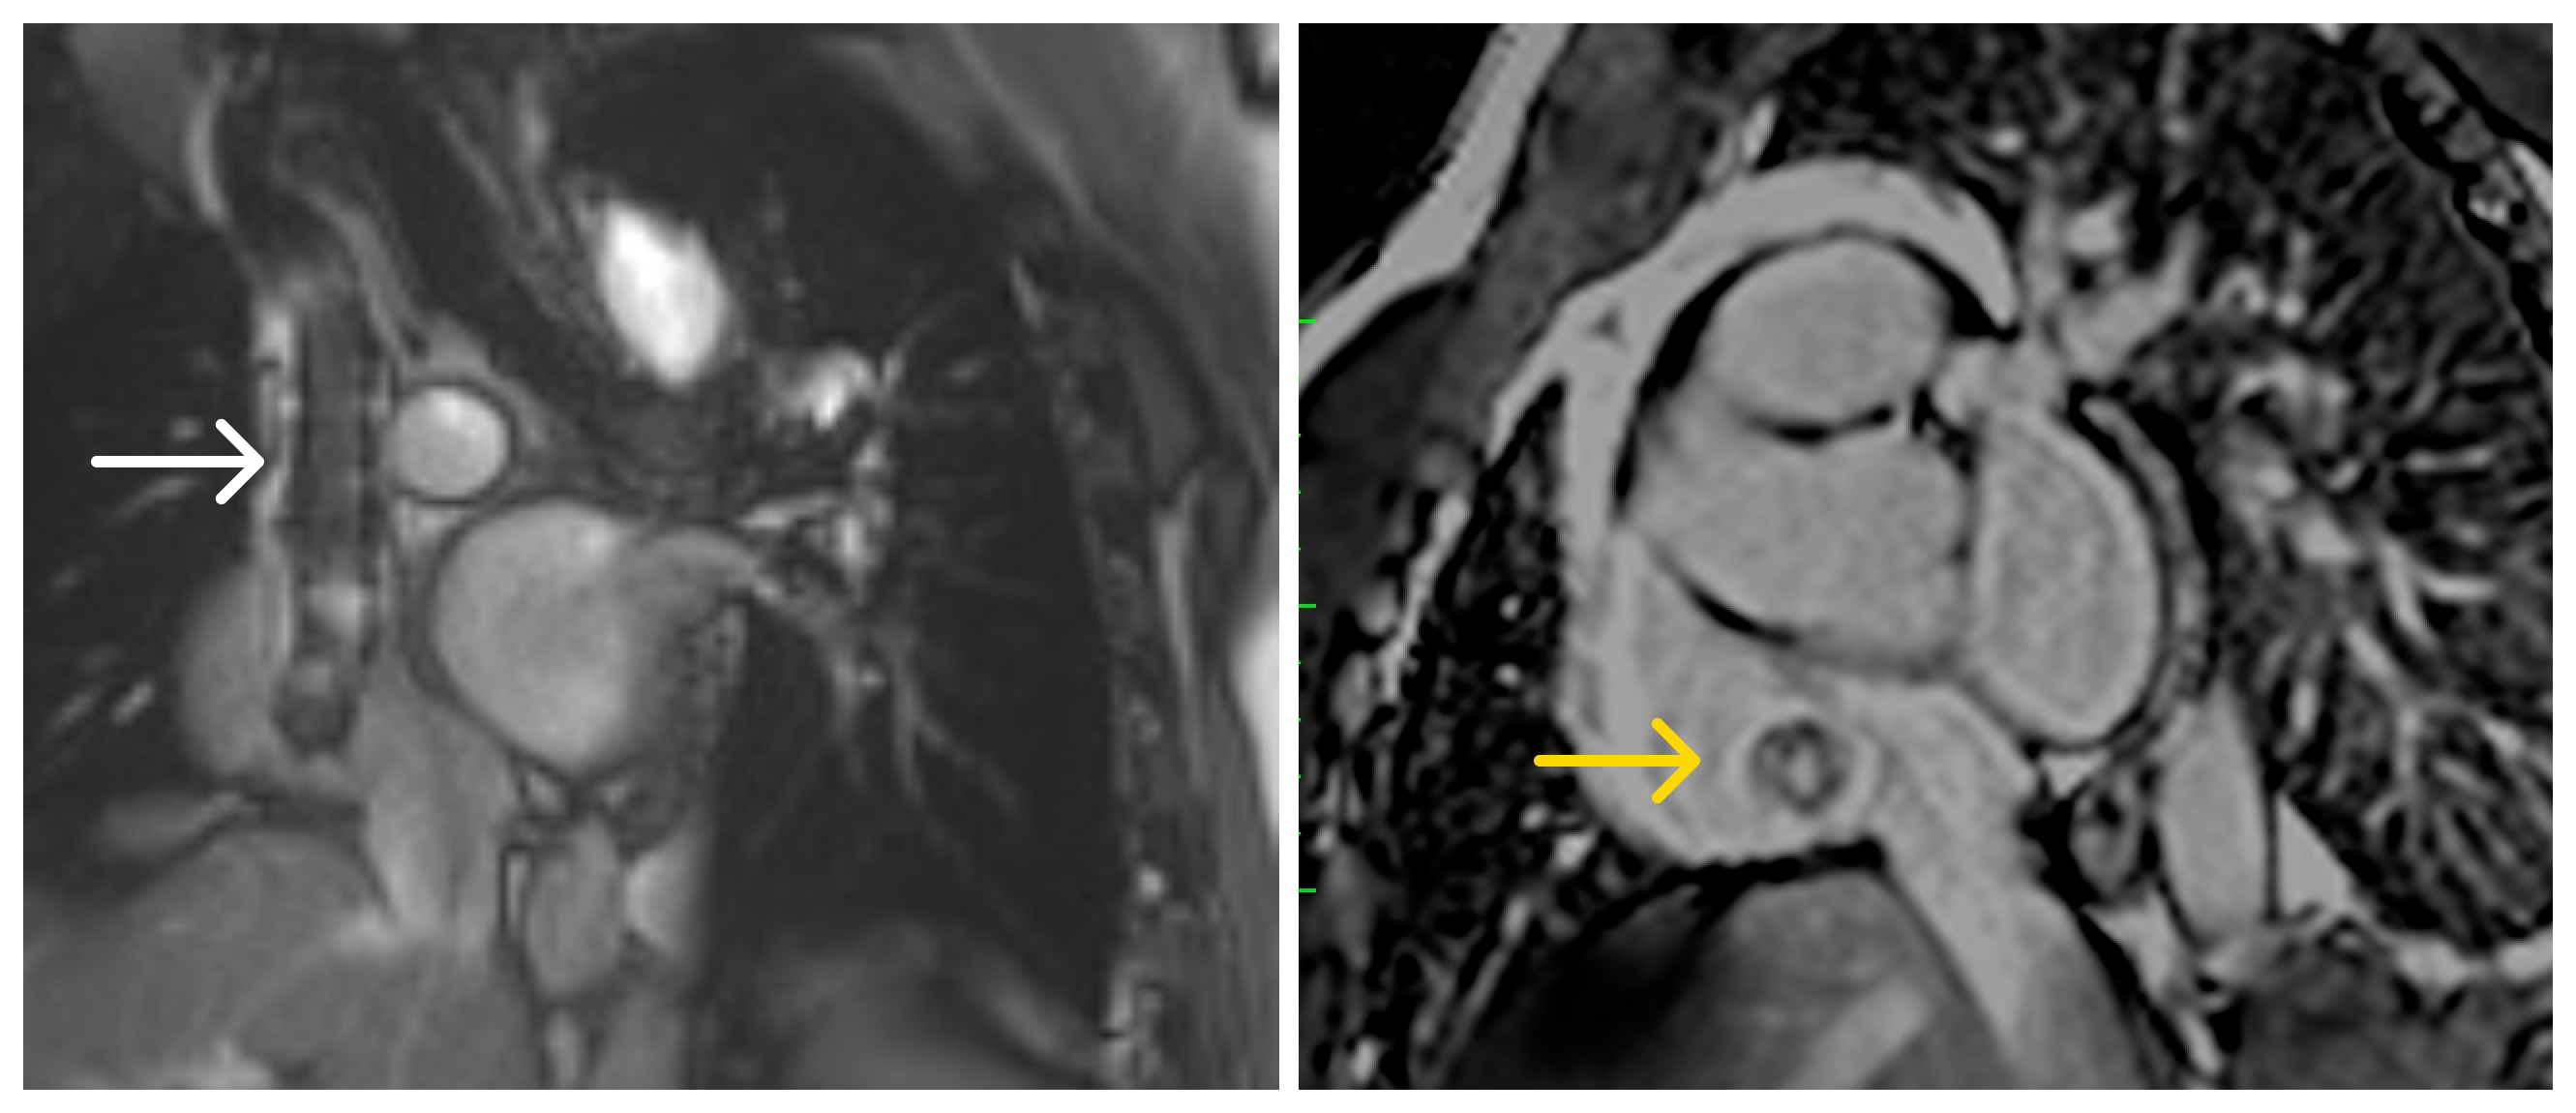

Image 2: Cardiac magnetic resonance. Left: tubular structure in the SVC with susceptibility artifact extending into the RA (white arrow). Right: single-shot LGE PSIR demonstrating contrast opacification within the stent lumen, consistent with preserved flow (yellow arrow).